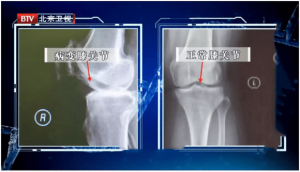

北京时间2022年9月20日凌晨,罗马俱乐部官方宣布,荷兰边后卫卡尔斯多普已经完成了左膝内侧半月板切除手术。

罗马俱乐部在官方公告中写道:“里克-卡尔斯多普今天接受了左膝内测半月板切除手术,由圣莫里茨医院的Georg Ahlbäumer医生主刀并成功完成手术。球员将留在瑞士继续治疗,然后很快在贝尔纳迪尼体育中心进行康复训练。”